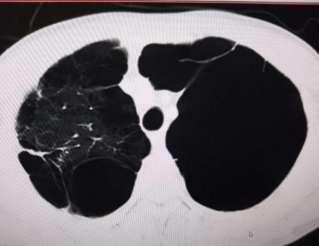

胸部CT发现华先生两侧肺都有葫芦样的巨大肺大疱,他两侧能正常呼吸的肺还不到50%。雪上加霜的是除了这些巨大肺大疱以外,在其周围还散在较多大小不一的肺大疱,就如同一张千疮百孔的渔网,破烂不堪。长久以来胸闷气短的原因也是因为这些肺大疱。

李晓辉仔细看了一下他的CT片,对华先生和他的家人说:“两肺多发、巨大肺大疱合并肺气肿,两侧大的肺大疱都有‘葫芦’那么大,尤以左侧特别明显,正常的肺也因此明显受压,有呼吸功能的不到50%,肺质量确实差。”

经过充分的术前准备,李晓辉、谢林辉、秦锋胸外甲乳科手术团队成功对华先生实施单孔胸腔镜微创手术,术中证实了术前的判断,华先生的左上、下肺间胸腔内长有多个巨大肺大疱,其内充满着高压气体,将左上、下肺大部压扁,导致功能丧失(如下图),左上肺周围还散在多处病变,如同“蜂窝”样改变,并同胸腔形成多处致密粘连。李主任小心细致地剥除粘连,将多处无用的明显病变彻底切除,让左上、下肺正常复张。。后胸膜摩擦促进胸膜腔粘连。